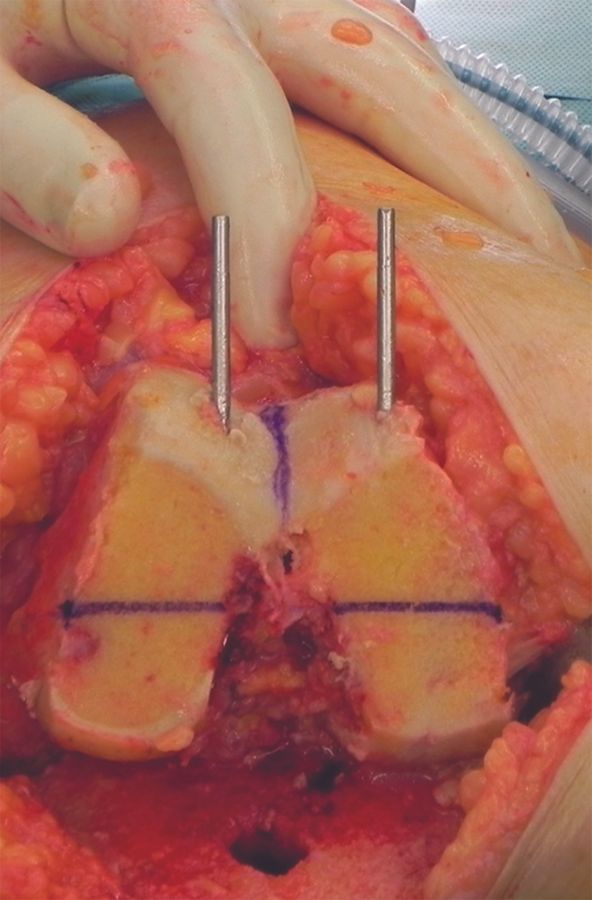

Resection of the amount of bone to be replaced by the implant takes place from the proximal tibia (9 mm from the lateral side) and from the distal femur (9 mm from the prominent side) in accordance with the preoperative planning. The marked TEA and Whiteside line on the distal femur resection represent additional landmarks for the ligament-based femoral rotation (balanced gap technique) (Figure 5), which will be described later.

An essential step of this functional alignment technique is the removal of any lateral, medial and accessible posterior femoral osteophytes before balancing the ligaments, in order to avoid any influence of the osteophytes on ligament tension [7,8] (Figure 6).